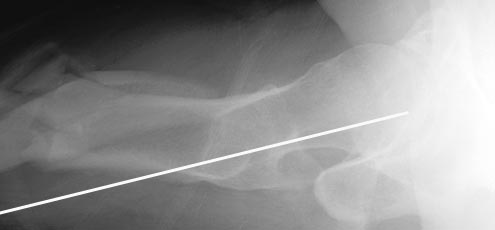

При многооскольчатых переломах стержень может "выпасть" кзади под

весом кондуктора и своим, даже если поначалу он вводился

правильно. Чтобы эту неприятность предупредить, стоит ввести спицу по

оси шейки бедра вдоль ее задней стенки, типа как на картинке. Если

стержень кпереди от этой спицы вводить, то он за нее не провалится.